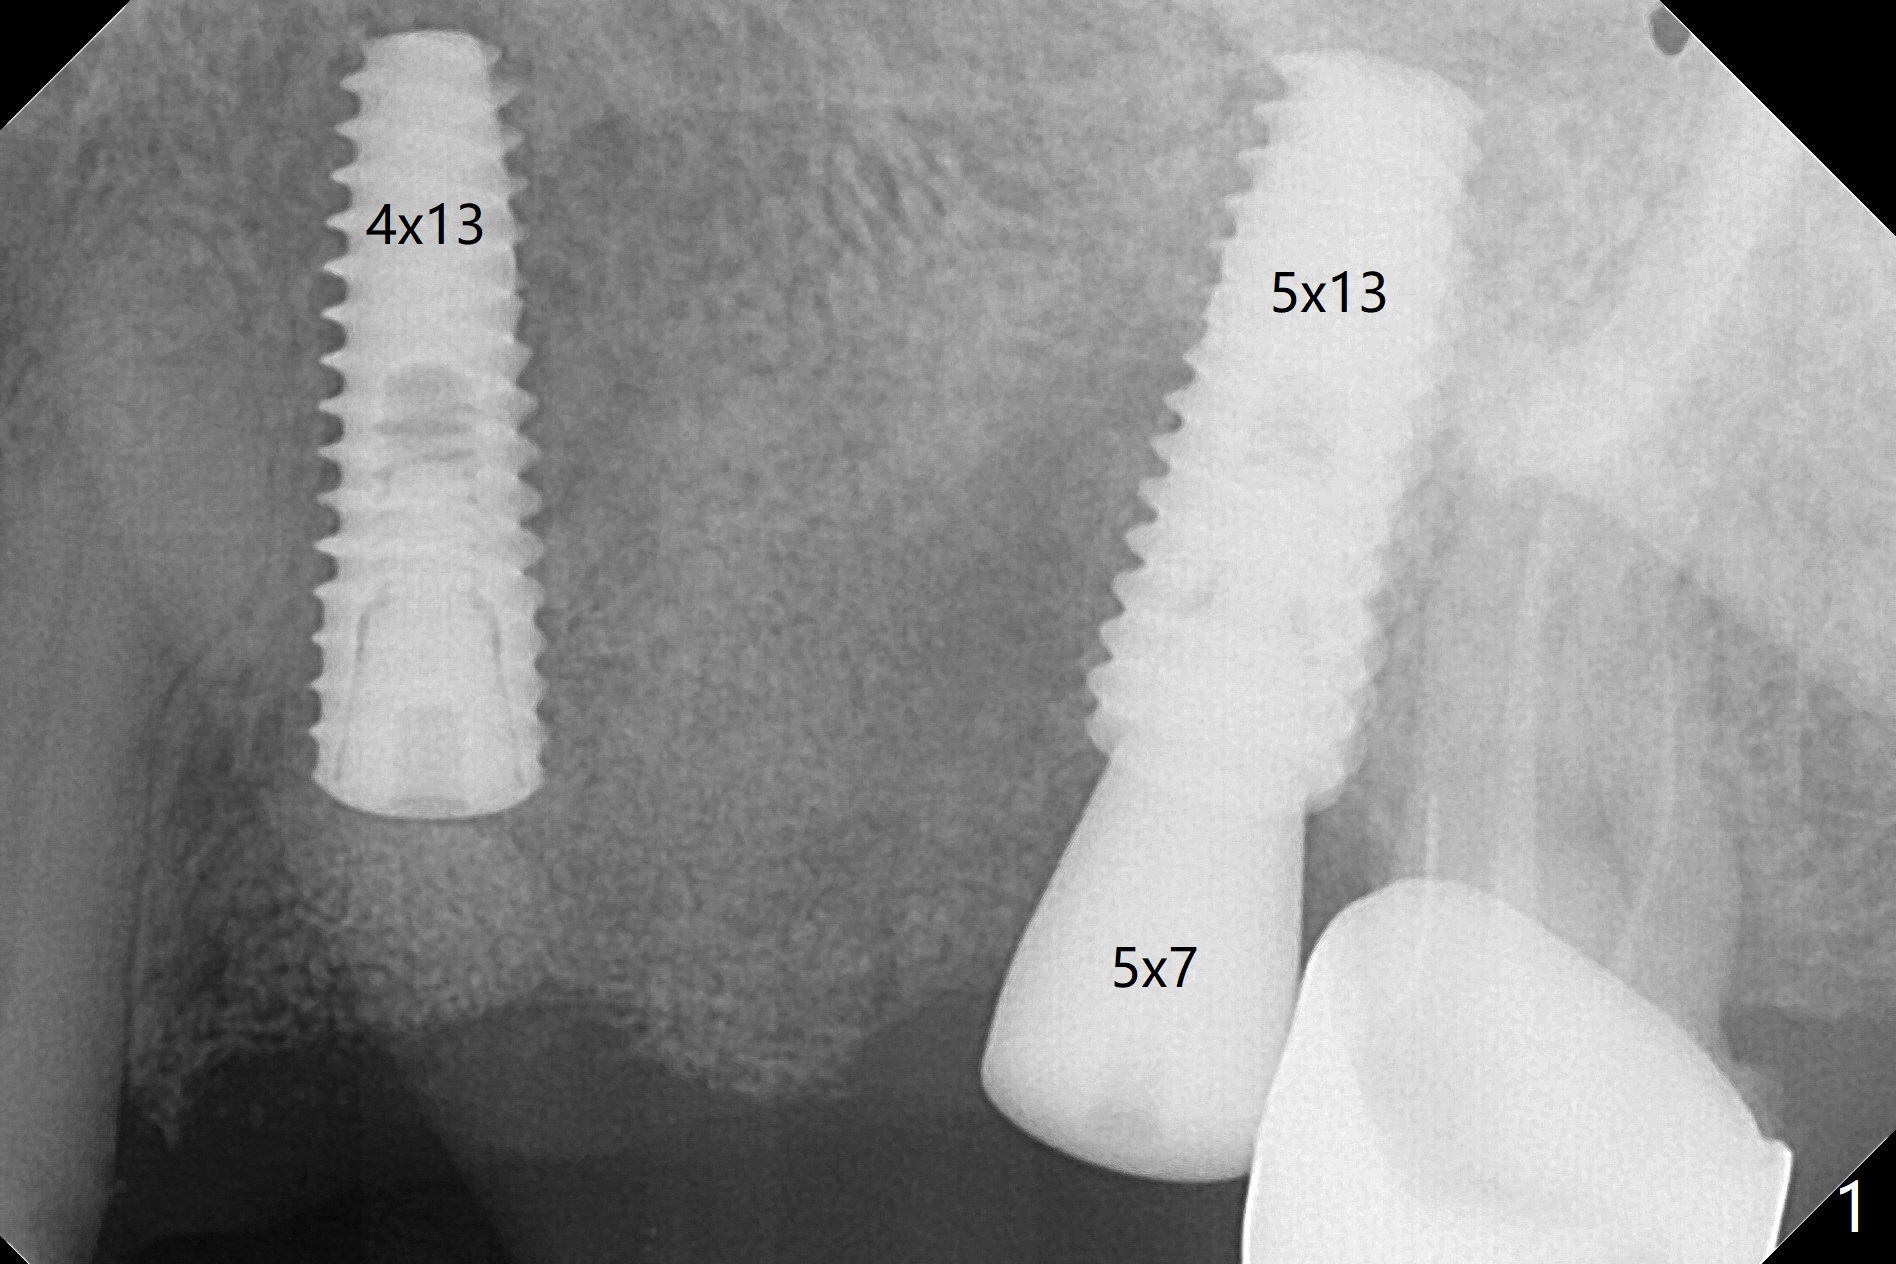

A 55-year-old woman had Hiossen implants (4x13, 5x13 mm) placed at #12 and 14 in China > 6 months (Fig.1,2). The fixtures are placed deep and un-parallel mesiodistally. After SRP UL, the implant at #12 is uncovered, followed by 4.6 and 5.5 mm profile drills and 5.5x7 mm IS healing abutment. The healing abutment at #14 is changed from 5x7 mm to 6.8x7 mm for easy impression later on. Due to coronavirus, the patient returns 8 months later. Oral hygiene is poor. The gingival cuffs at #12 and 14 are erythematous and edematous. UF cemented abutments have to be placed (Fig.3-5) because of equi-gingival fracture of #3 and 4 splinted crowns. In fact the straight abutments are not parallel buccopalatally. Buccoocclusal reduction is done at #12 for provisional FPD. SRP will be performed with #11 DL composite prior to impression.